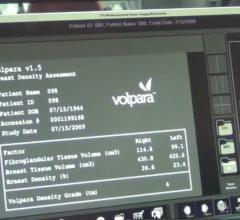

Volpara Solutions will exhibit its complete suite of quantitative breast imaging tools built on the Volpara Solutions software engine that allows for personalized measurements of volumetric breast density, patient-specific dose, breast compression and other factors designed to maintain accuracy and consistent quality in breast screening.